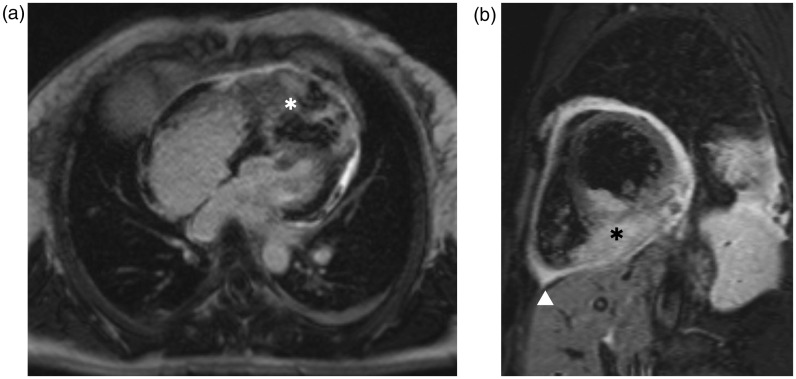

我们报告一例33岁的妇女因呼吸困难和发烧而紧急入院。病史包括完全缓解的宫颈鳞状细胞癌。胸部增强计算机断层扫描(CT)显示浸润性心脏肿块,表明可以排除肺炎。通过超声心动图和心脏磁共振成像(MRI)进一步评估肿瘤显示经壁浸润的顶室间隔,肿块延伸到左、右心室腔。这个肿块高度怀疑是心脏转移。宫颈癌引起的心脏转移极为罕见。复发的宫颈癌累及心脏应考虑,即使在治疗方法。无创成像在心脏肿块的检查中起着至关重要的作用。超声心动图、CT和MRI是心脏内病变完整检查的互补成像方式。

We report a case of a 33-year-old woman with emergency admission due to dyspnoea and fever. History included squamous cell carcinoma of the cervix in complete remission. Contrast-enhanced computed tomography (CT) scanning of the chest, which was indicated to rule out pneumonia, revealed an infiltrative cardiac mass. Further assessment of the tumour by echocardiography and cardiac magnetic resonance imaging (MRI) showed transmural infiltration of the apical interventricular septum with a mass extending into the left and right ventricle cavities. The mass was highly suspicious for a cardiac metastasis. Cardiac metastases from cervical cancer are extremely rare. Recurrence of cervical carcinoma involving the heart should be considered even after a curative therapy approach. Non-invasive imaging plays a paramount role in investigating cardiac masses. Echocardiography, CT and MRI are complementary imaging modalities for complete work-up of intracardiac lesions.